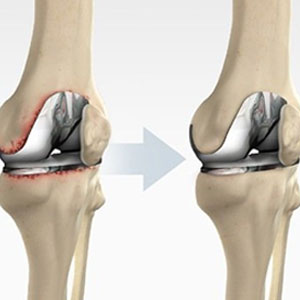

Arthroplasty, also called joint replacement, is surgery to replace a damaged joint...

Total knee replacement is one of the most successful procedures in all of medicine...